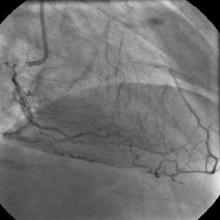

Angiography

1) RCA: Discrete severe mid stenosis (Figure 1)